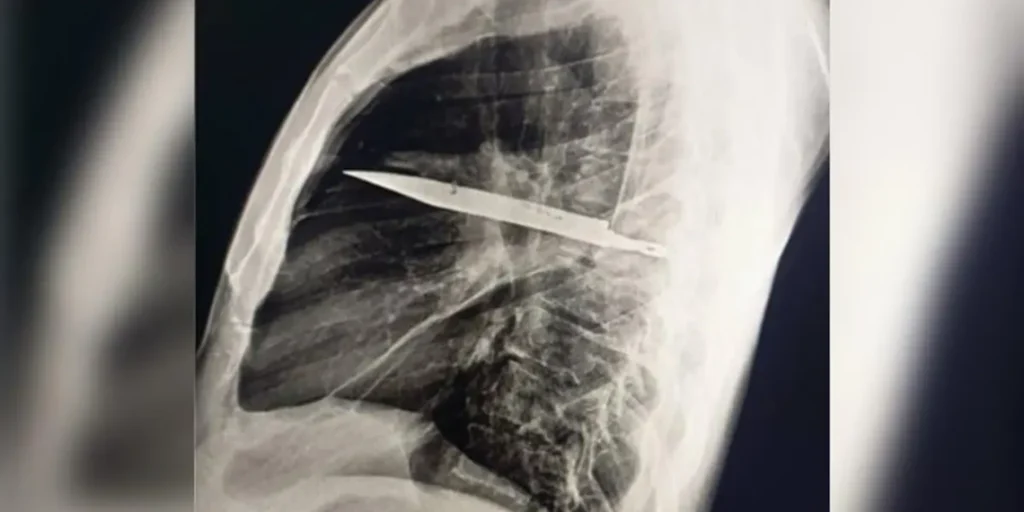

Surpresa no raio-x

O exame atual mostrou que uma lâmina estava presa ao lado direito do tórax, encostada à escápula. Apesar do tamanho, não atingiu órgãos vitais. Segundo os médicos, o acúmulo de pus foi causado pela presença do corpo estranho e por tecido danificado ao redor.